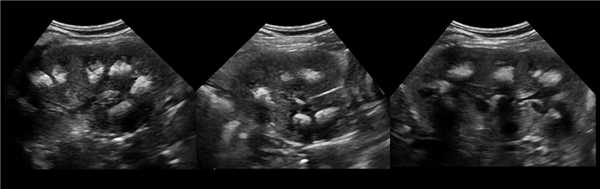

Рисунок. На УЗИ (1) и КТ (2, 3) контур почек волнистый. У эмбриона почка развивается из отдельных долек, которые сливаются по мере их роста. Дольчатое строение почек хорошо видно у плода и новорожденных, в единичных случаях сохраняется у взрослых.

Рисунок. Можно встретить горбатую левую почку — выпуклый неровный наружный контур из-за гипертрофии паренхимы в средней трети почки. Считают, что «горб» формируется у плода под давлением нижнего края селезенки.

Рисунок. Сканирование со стороны передней брюшной стенки позволяет не пропустить перешеек между почками. Перешеек спереди от позвоночника является доказательством сращения почек — подковообразная почка. Варианты анатомии подковообразных почек смотри здесь.

Рисунок. На УЗИ округлое образование разделяет почечный синус на два сегмента с общей лоханкой; междолевые артерии огибают образование; эхогенность и интенсивность сосудистого рисунка внутри близка корковой зоне. Заключение: Гипертрофия колонны Бертини или неполная паренхиматозная перемычка. Это вариант нормального строения почки. Термин «неполное удвоение ЧЛК» неверный, т.к. неполная паренхиматозная перемычка не является признаком удвоения ЧЛК.

Рисунок. На УЗИ синус почки разделяет полная паренхиматозная перемычка (1, 2). В таких случаях разграничить удвоение почки от гипертрофии колонны Бертини поможет экскреторная урография. Удвоенная почка покрыта общей фиброзной капсулой. Полное удвоение предполагает наличие двух лоханок, двух мочеточников и двух сосудистых пучков. Неполноудвоенная почка (3) питается одним сосудистым пучком, мочеточник может быть удвоен вверху и впадать в мочевой пузырь одним или двумя устьями. Удвоение ЧЛК и мочеточников — фактор риска развития патологии (пиелонефрита, гидронефроза и др.).

Рисунок. На УЗИ синус почек широкий, неоднородной эхоструктуры (1, 2). На фоне гиперэхогенного жира гипоэхогенный очаг округлой формы (2), при ЦДК междолевые сосуды проходят через гипоэхогенную зону без смещения (3) — это гипоэхогенный жир. При ожирении липоматоз синуса можно ошибочно принять за атрофию паренхимы.